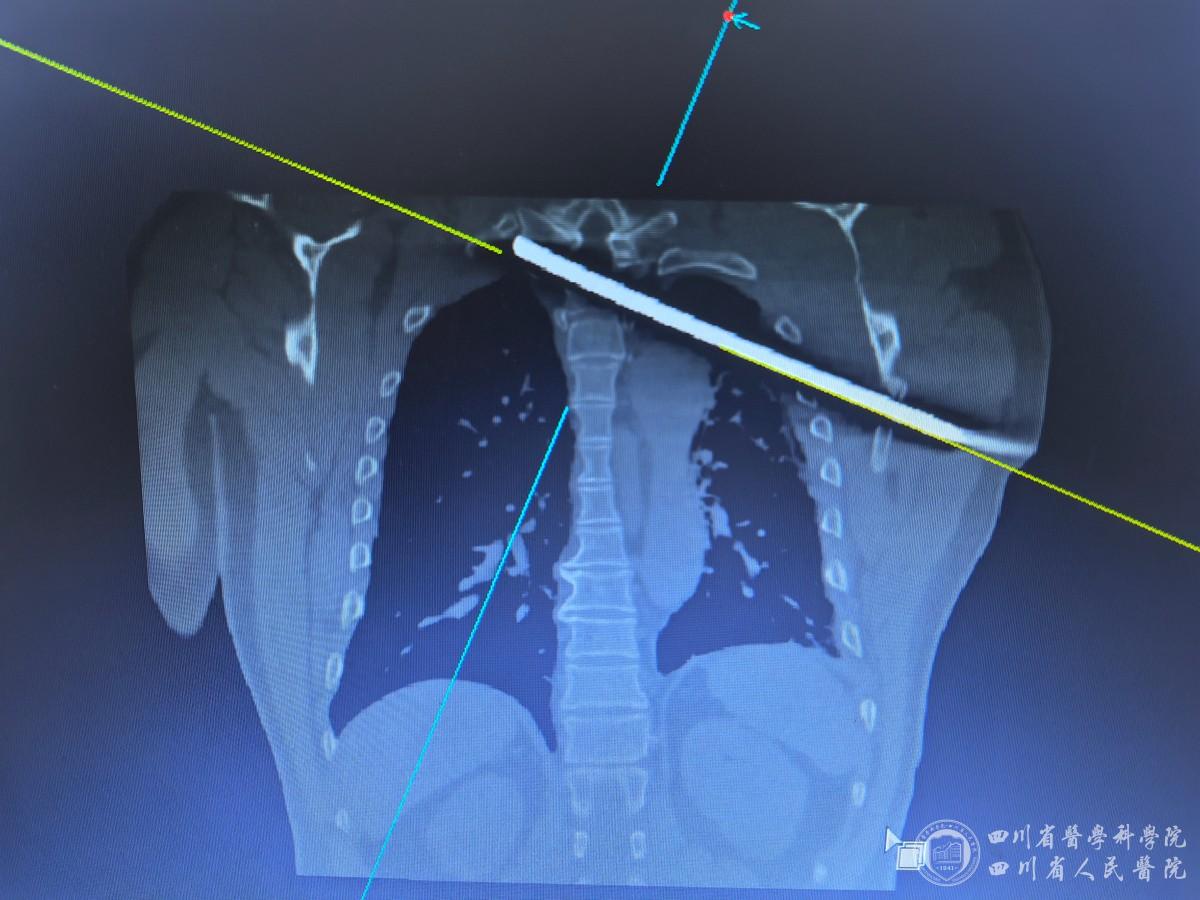

11月17日晨,伤者刘先生(化名)高空作业时意外坠落,被一根螺纹钢斜向贯穿后动弹不得。钢筋自他左侧腋下穿入,斜向横穿整个胸腔直达右侧肩颈部皮下。剪断体外的钢筋后,工友们迅速将刘先生送往眉山市人民医院救治。因伤情严重,眉山市人民医院医生联系到我院骨科主任医师张伟。

患者术前影像与床旁评估明确“紧贴主动脉弓、穿过椎管、贴近脊髓”的极高风险路径,团队将“防大出血、防二次神经损伤”设为首要目标。确定“先控险稳态、分步清创取出、同步修复重建”的方案。麻醉科快速建立安全气道与多通道静脉通路,完善大出血应急预案与血液管理,实时维护循环与呼吸稳定。胸外科清理胸腔损伤、修补受损肺组织,充分暴露并避开主动脉弓与相关大血管,建立安全手术通道。骨科在实时影像和神经功能监测配合下,沿钢筋通道逐层松解,精准脱嵌,避开脊髓与神经根,完整取出异物;随后实施椎体复位与稳定重建,最大限度降低二次损伤。

18日凌晨1时许,手术开始。由于钢筋紧贴主动脉弓与脊髓,手术每一步均在毫米级精度下推进。团队以影像导航与神经监测为“眼睛”,以多学科同步沟通为“刹车”,逐步解除粘连与嵌顿。在确认与大血管、脊髓的安全间隙后,骨科完成异物完整、可控地退出;胸外科同步监护主动脉弓周围区域,严防突发出血。随后,由骨科完成椎体复位与稳定性重建,保护神经结构,尽量减少组织创伤。